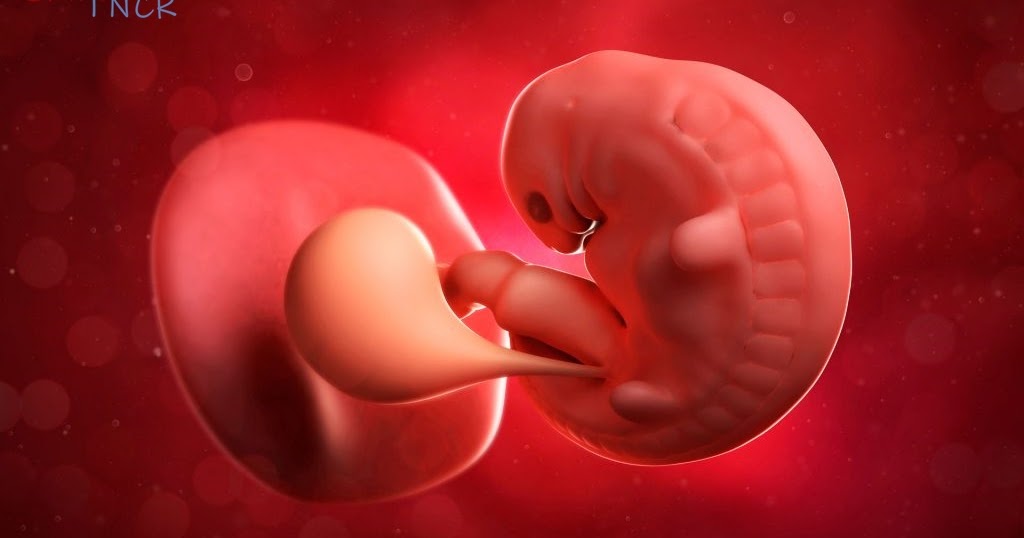

1 aylık Bebek fotoğrafları, Bebek, Fotoğraf From Pinterest

1 aylık Bebek fotoğrafları, Bebek, Fotoğraf From Pinterest

1 aylık Bebek fotoğrafları, Bebek, Fotoğraf